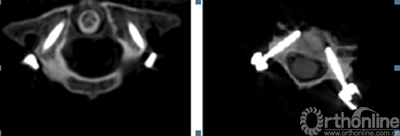

通过Geomagic studio12参考最佳进钉点所在的位置,提取椎体后部解剖形态,设计与椎板后部解剖形态一致的反向模板(图2),与椎弓根植钉通道拟合为一体,形成带有定位定向管道的数字化导航模板。在三维重建椎体模型上即可以进行虚拟植钉手术操作。再通过光固化成型技术(SLA)生成实模板体即可以辅助术中应用。在临床应用时可以确保每一枚螺钉正确的置入位置和方向(图3),真正体现了颈椎椎弓根螺钉置入的个体化原则。我们的临床应用范围已经包括了从上颈椎、胸腰椎到脊柱侧弯矫形等多个方面。

辅图 尸体标本经模板辅助椎弓根植钉后的CT影像显示椎弓根钉位置良好

临床研究发现,每个导航模板都和相应椎体后部骨性解剖结构十分贴合,所有椎弓根螺钉置入较为满意。术后CT扫描发现椎弓根螺钉完全位于椎弓根内,进钉点准确、进钉角度恰当,螺钉长度及直径合适,无穿破椎弓根皮质及椎体前方的螺钉,患者无周围组织损伤症状。个体化的脊柱椎弓根导航模板对于手术医师只要将模板和暴露的椎板相贴合, 就可以进行钉道准备, 并不依赖于个人经验。模板的制作是个体化的制作, 可采用定制的方式, 因此临床上有应用方便,为颈椎椎弓根的定位提供了一种全新的方法。(如图4、图5)。

图4 术后X线及CT影像